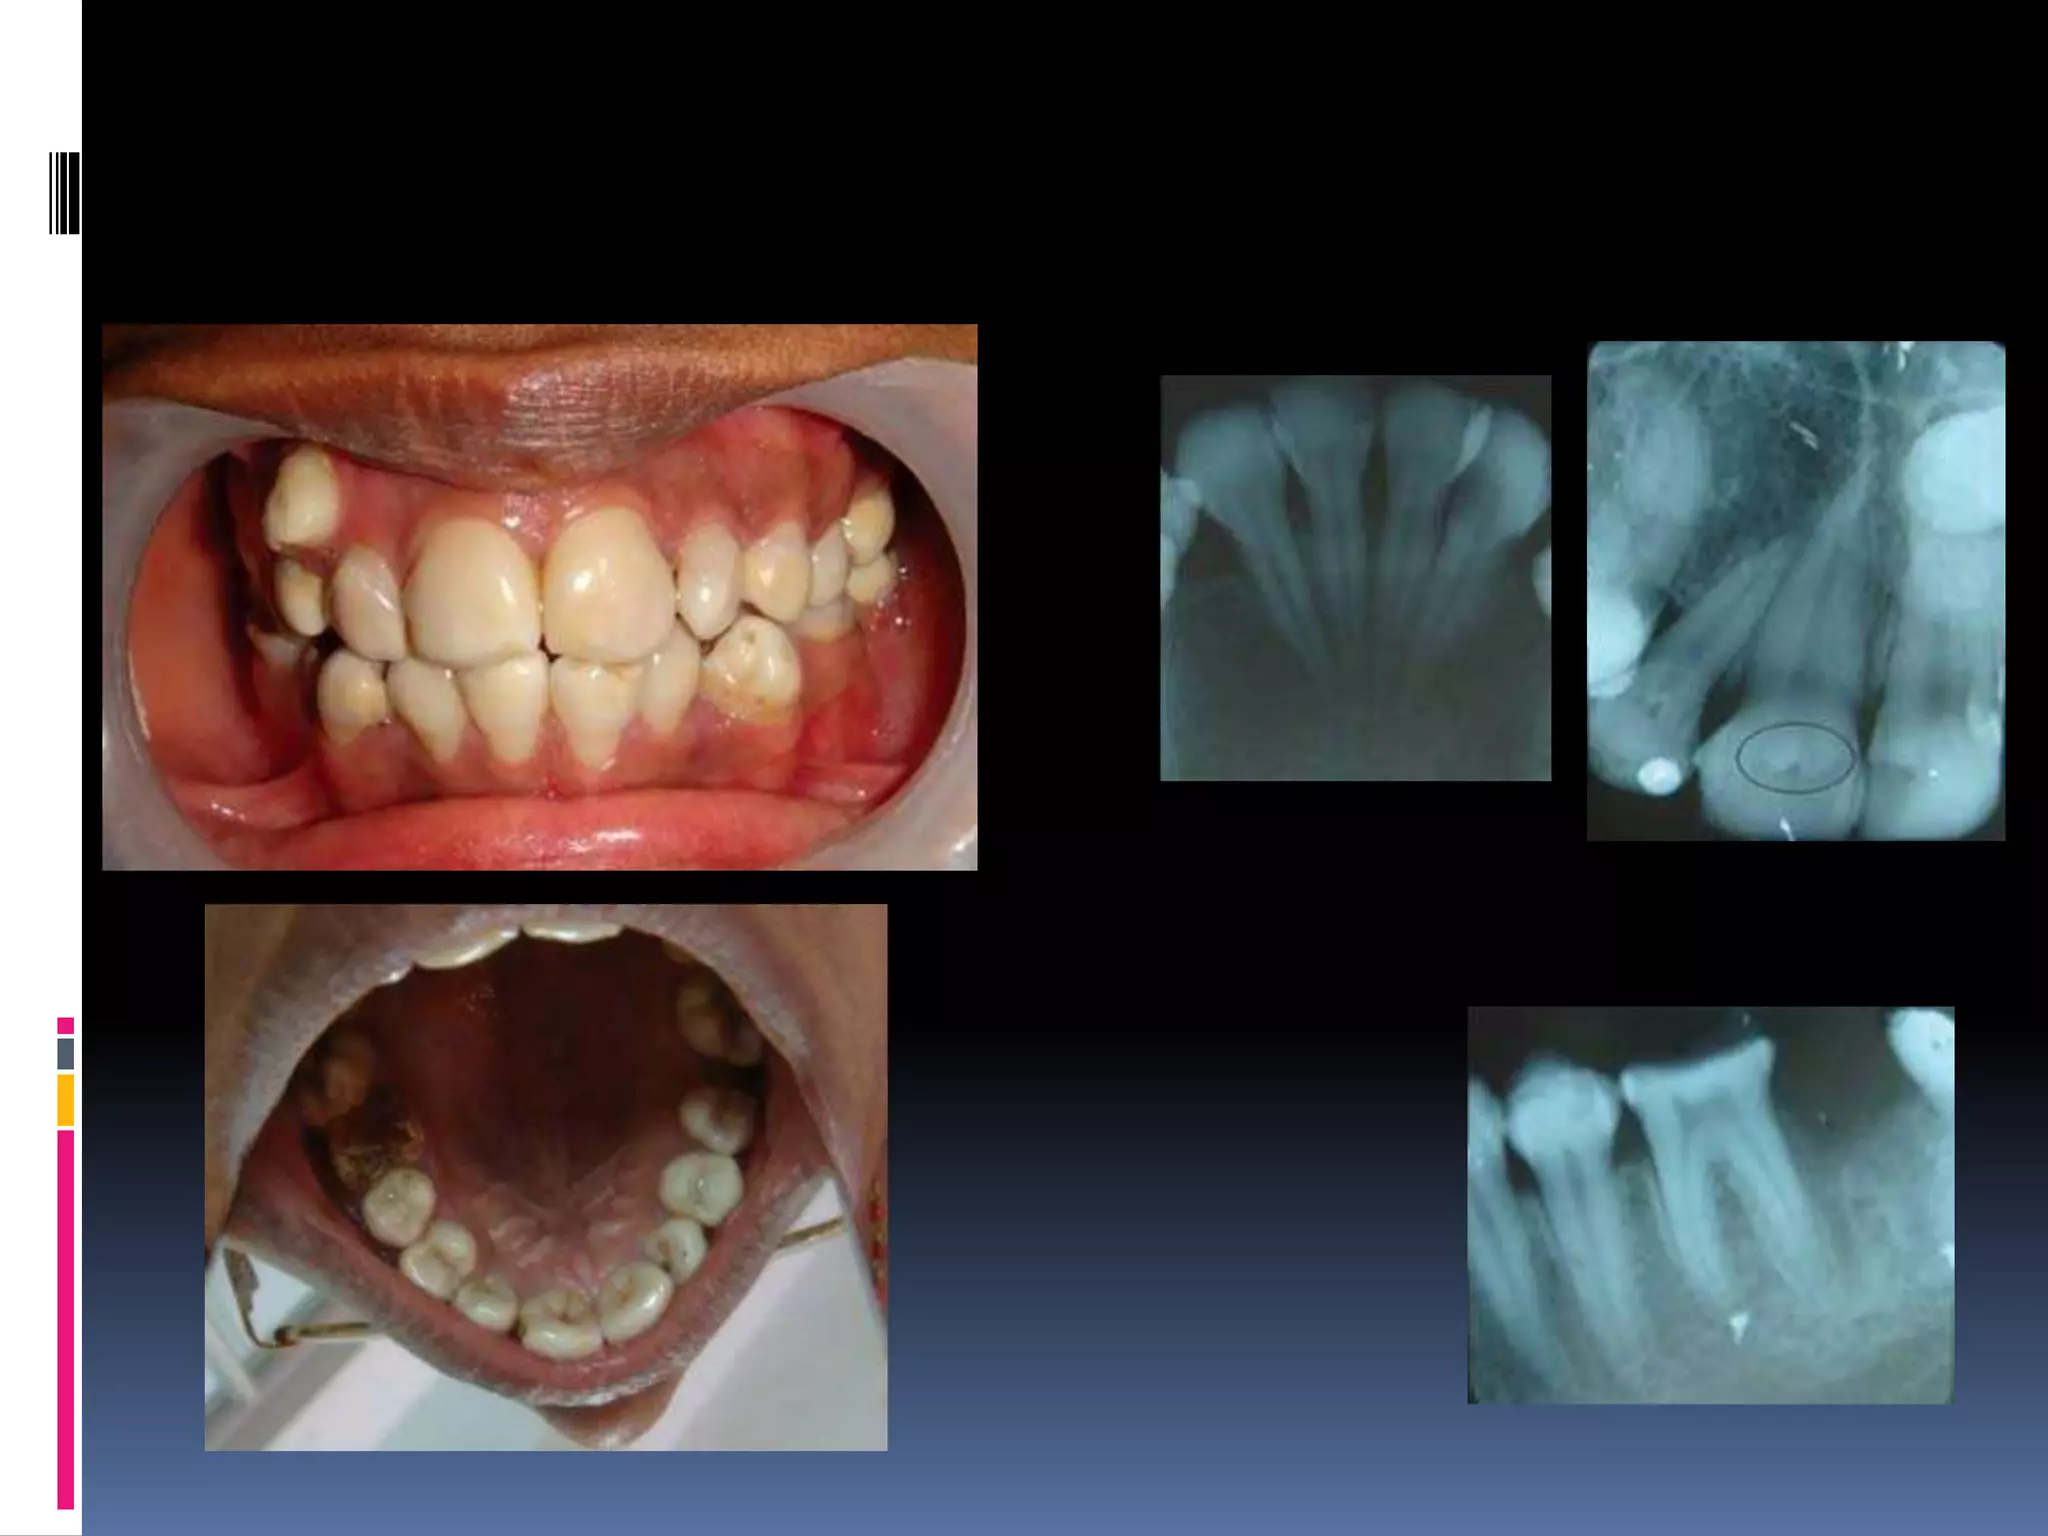

Dens invaginatus/dens

indente

A deep surface invagination of crown/root

lined by enamel.

Due to invagination of surface of tooth crown

before calcification occurred.

 > max laterals

 i)coronal dens invaginatus:

 Type I – invagination confined to crown.

 Type II – extends below CEJ but not

communicating with pulp.

Type III – extends through root & perforate

apical / lateral radicular area.

 Tooth with in tooth

ii) radicular dens invaginatus –

 Arise secondary to

proliferation of hertwig’s

root sheath , with

formation of enamel

extending along surface of root.

 Enamel deposition simillar to enamel pearl.

 R/F – enlargement of root

 dilated invagination lined by enamel &

opening of invagination along lateral aspect

of root.

 Mild form – pear shaped invagination of

enamel & dentin

Palato gingival groove

 Associated with periodontal defect